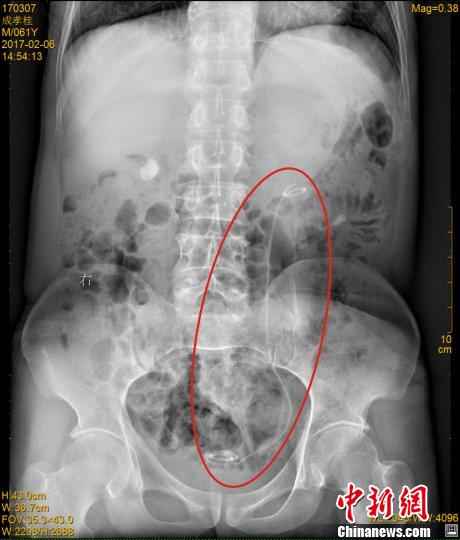

在医院接受B超检查时,医生发现成先生双肾均有结石、严重积水,此外,其左侧腰部还有一根条状物。在拍摄了X光片后,医生才发现,成先生体内竟然遗留着一根医用导管(双J管)。医生仔细询问后,成先生终于想起自己7年前接受过手术,这意味着这根长达30多厘米的导管,在其体内隐藏了7年时间。

2月9日,医生小心翼翼地从成先生体内取出了这根双J管。取出的双J管上,附着很多结石沉渣,原本白色的导管已变成黑色。取出导管后,医生又将其左肾中约1.5x1厘米大小的结石粉碎取出,然后重新置入了一根全新的导管。